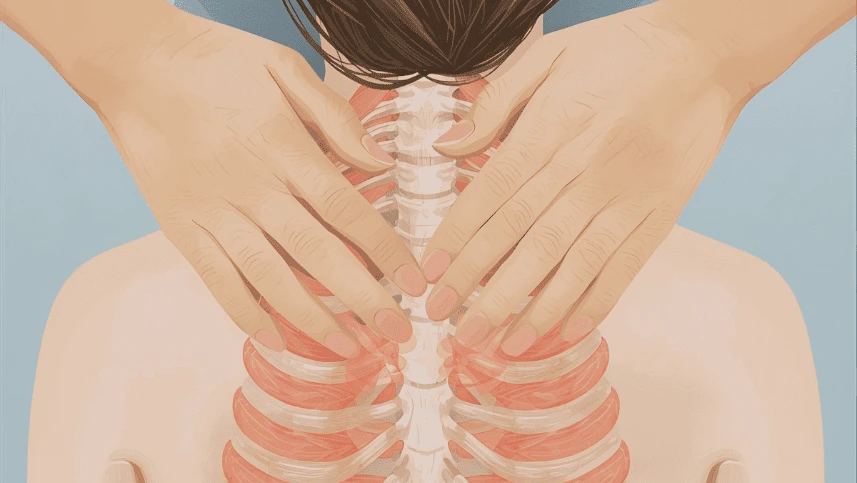

A microfisioterapia é uma técnica de terapia manual realizada por meio de toques leves e precisos na pele. Esses estímulos permitem ao fisioterapeuta identificar marcas de traumas antigos armazenados nas células — registros que podem ter origem em situações de estresse, choques emocionais ou até doenças que deixaram impactos no corpo. Com o tempo, essas marcas influenciam não apenas a saúde física, mas também o equilíbrio emocional.

3. O Papel da Fáscia e a Comunicação Corporal

A fáscia é um tecido conjuntivo que envolve todos os órgãos, músculos e nervos. Ela funciona como uma rede de comunicação rápida. Estudos modernos mostram que a fáscia armazena tensões mecânicas e bioquímicas. Através do toque sutil, o terapeuta acessa essa rede para liberar restrições que impedem o fluxo de saúde.